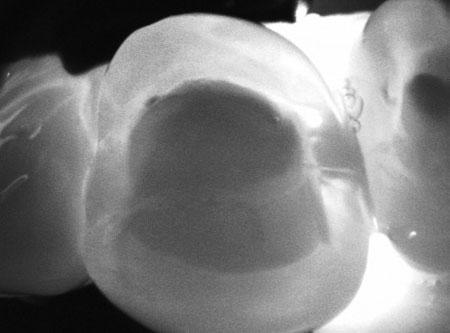

CariVu (Infrared Transillumination)

Another invaluable technology is called CariVu. CariVu uses infrared illumination to make your dental enamel appear translucent. This actually allows Dr. Rychetsky to see through the tooth to expose its structure and illuminate decay (caries) inside the tooth in its earliest stages.